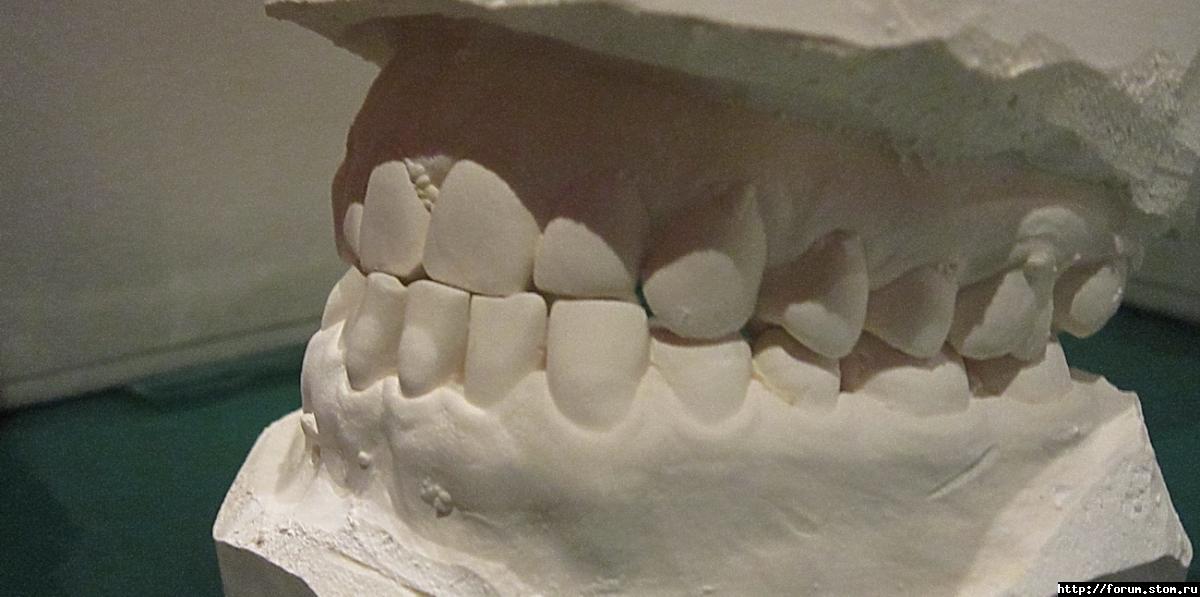

Inn-ka Опубликовано 6 ноября, 2011 Поделиться Опубликовано 6 ноября, 2011 (изменено) Добрый день, Уважаемые.Есть проблема - мезиальный прикус, передие нижние зубы перекрывают верхние.Мне 30, понятное дело, если ставить брекеты - хотелось бы лингвальные.Не совсем понятно - целосообразно ли, при моей проблеме ставить лингвалки.Пока была на консультации только у одно ортодонта.Доктор долго мялась, говорила: "эх, сделать быть операцию, чуть-чуть чик и все"."чикать" не получится, операцию мне делать нельзя.Да и масштаб проблемы не такой, чтобы решиться на такие кардинальные меры.Затем, доктор сказала: "ну ладно, тогда установим микроимплант и будем нянуть зубы в обратном направленинии".В общем - ищу других докторов, хочу услышать различные мнения.Понимаю, что мой волевой подбородок останется при мне, да и не отраляет от мне жизнь.Мне бы зубы выровнять. Это-то, надеюсь возможно?Кстати, энное количество времени назад одну нижнюю восьмерку удалила, смотрю, скученность со стороны удаления восьмерки, стала менее выражена. Собираюсь с духом удалить вторую. Уж очень травматично и болезненно в первый раз получилось. :-(Буду очень благодарна специалистам за советы. Изменено 6 ноября, 2011 пользователем Inn-ka Ссылка на комментарий

Премоляр Опубликовано 6 ноября, 2011 Поделиться Опубликовано 6 ноября, 2011 "Мне бы зубы выровнять. Это-то, надеюсь возможно?"-конечно возможно Профиль конечно не изменить,ибо работа будет только на зубоальв.уровне путем компенсации.С точки зрения эстетики вас устроит результат,но с точки зрения функции и стабильности результат может не устроить доктора Ссылка на комментарий

Force Опубликовано 6 ноября, 2011 Поделиться Опубликовано 6 ноября, 2011 Без операции возможно пролечить либо с удалением премоляров нижней челюсти, что не есть хорошо, либо с использованием техники многопетлевой дуги. До http://i051.radikal.ru/1109/68/9299be8a9a53.jpg После http://s009.radikal.ru/i307/1109/30/2152edffbc4f.jpg В последнем варианте профиль меняется незначительно, но эстетика и функция восстанавливаются. К сожалению, о лингвальных брекетах речи и быть не может.(только вариант 1, но там много нюансов). Ссылка на комментарий